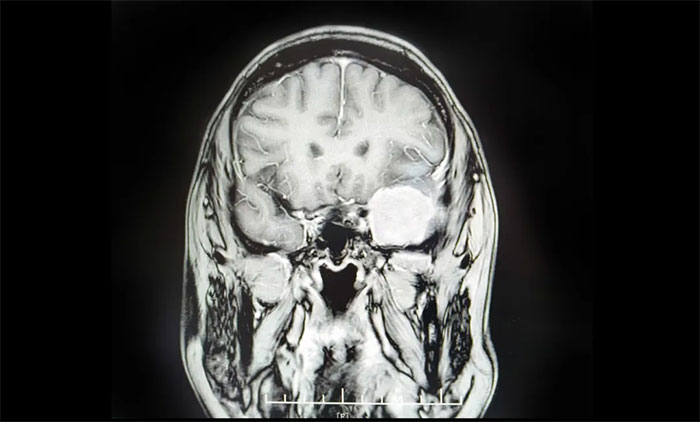

张女士的病例极具警示意义。两年前体检发现“颅内占位”,因担心手术风险选择了保守治疗。今年6月下旬,她突发持续性头晕,两周未缓解,预感不妙,遂前往上海蓝十字脑科医院求诊。

检查证实为左侧蝶骨嵴脑膜瘤。该肿瘤位置极其凶险:紧贴左侧语言中枢和运动皮层,损伤可能导致失语或瘫痪;与大脑关键供血主干——大脑中动脉(MCA)及重要静脉窦紧密粘连;深埋于蝶骨嵴颅底,手术视野狭窄,难度巨大。

最终,卢云鹤博士团队迎难而上,成功运用翼点入路手术,顺利切除了这枚4.5公分的巨大肿瘤。术后第二天,患者即肢体活动自如,言语清晰流畅,无新增神经功能损伤,目前正在康复中。